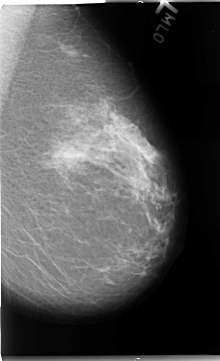

B_3103_1.RIGHT_CC

FILE: B_3103_1.RIGHT_CC.OVERLAY

TOTAL_ABNORMALITIES 1

ABNORMALITY 1

LESION_TYPE MASS SHAPE OVAL MARGINS CIRCUMSCRIBED-MICROLOBULATED

ASSESSMENT 3

SUBTLETY 4

PATHOLOGY BENIGN

TOTAL_OUTLINES 1

BOUNDARY